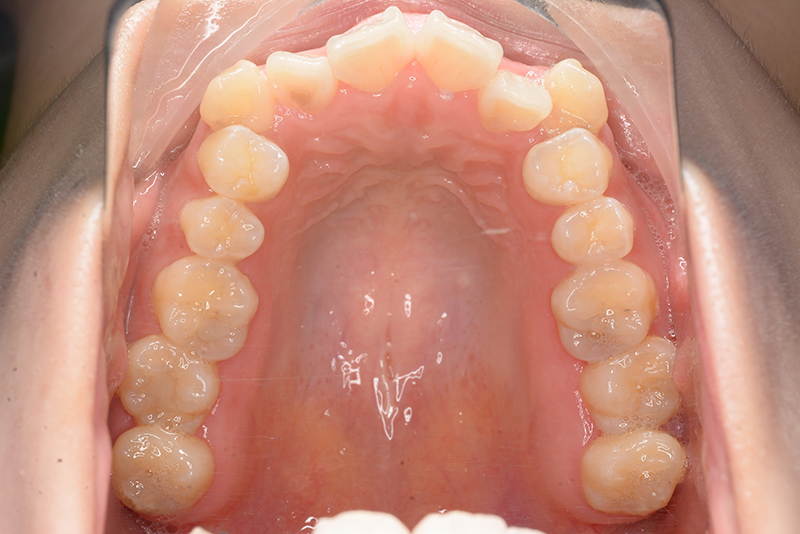

| 口腔内所見 | over jet 4.5mm、over bite 4.0mm、大臼歯関係 I級で上下顎前歯部に叢生が認められた。 |

| 批評・予后 | 叢生が大きかった影響もあり、治療期間は20ヶ月と比較的短い期間が終了できた。治療後においては口元の改善、咬合の緊密化は達成できたように思う。 |